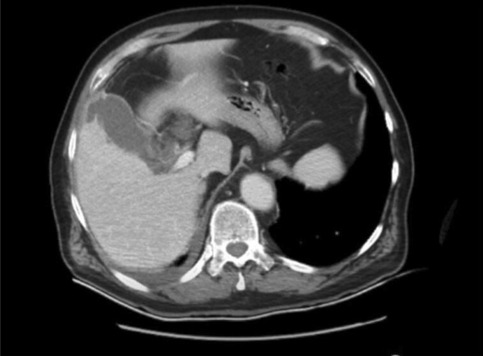

Result: The comparative analysis of the data shows a decrease in the number of presentations in ESU of AC cases during the pandemic, compared to the previous year, most often due to patients' fear of contacting the virus in the hospital environment. The median time between the onset of symptoms and the presentation in the ESU: 2020 – 14 days, 2019 – 5 days. Forms of moderate and severe AC predominated in the pandemic: GradeI—14.28%; GradeII—57.14%; GradeIII—28.57%. In 2019 GradeI—66.39%, GradeII—27.73%, GradeIII—5.88%. Laparoscopic cholecystectomy was attempted for all patients from the beginning, but the complications identified during surgery and severe forms led to a conversion rate in 2020 of 14.28%, compared to 5.88% in 2019. The severity of the cases is also observed in the postoperative complications encountered (perihepatic abscess Fig. 2. Figure 2, wound infection, bile leak; 2019—5.04%, 2020—23.21%), which required surgical reinterventions to solve them (2019: 2.52%, 2020: 10.71%). The number of deaths was significantly higher in 2020 (5.35%), compared to 2019 (0.84%).